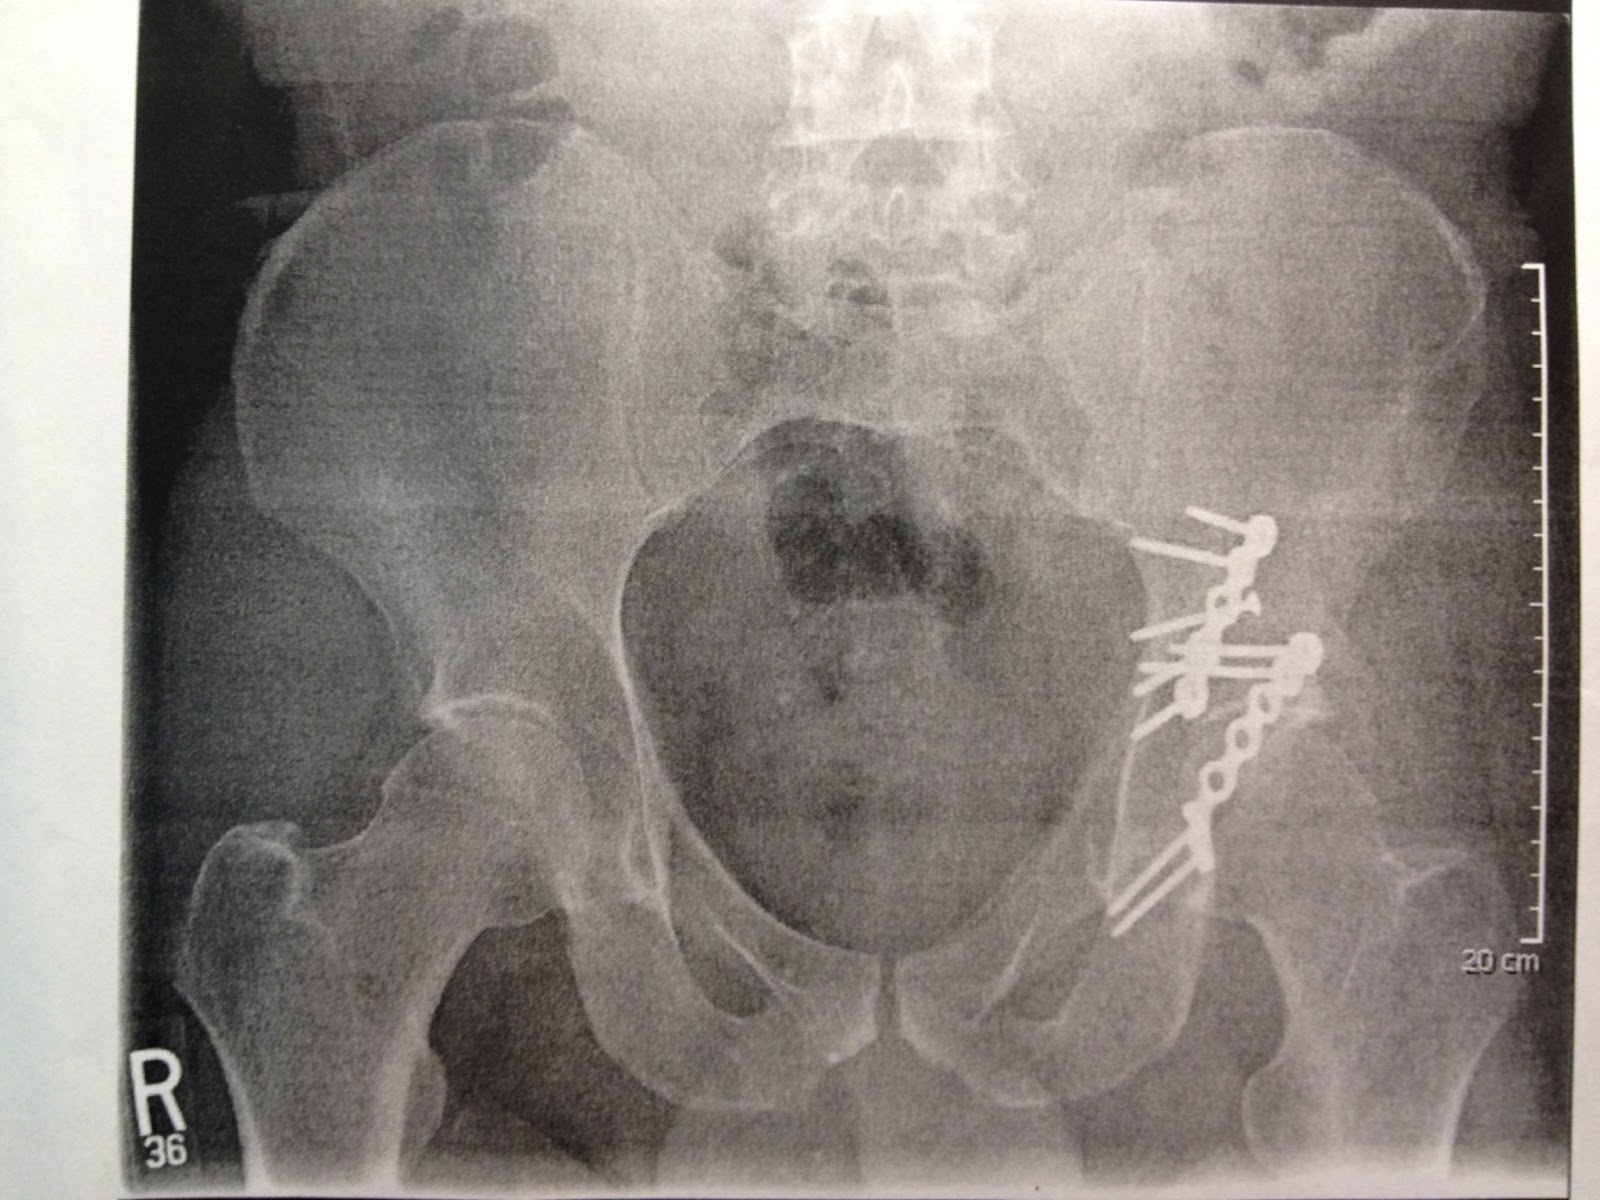

I don't think I've ever posted a picture of my pelvis post accident.  This is from 7/16/12, so three months after I broke it.  Those are some nice nails and plates on my left.  The scale on the right of the picture says 20 cm, so I think the one is 12 cm long and the other is about 7 cm.  So about 7.5 inches end to end, with overlap?  The scar is about 12-13 inches, so they had some working space.  Glad they didn't have to re-operate to put the extra plate/s in for reinforcement.  This seems like more than enough.